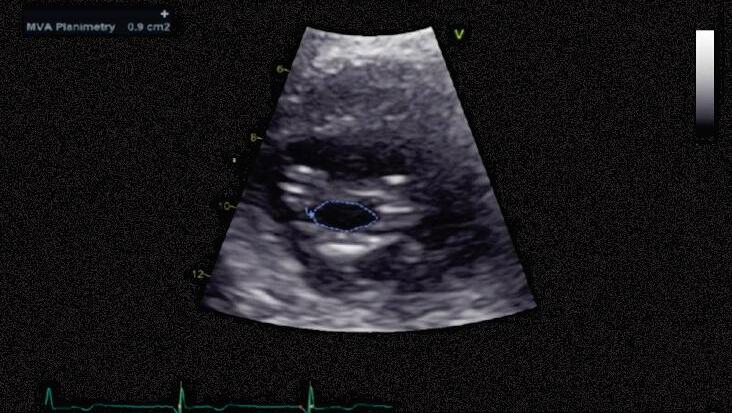

30. (Título de Especialista em Cardiologia) Jovem com queixa de fadiga e dispneia. Ao exame, apresenta bom estado geral e pulsos normais. À ausculta: primeira bulha hiperfonética, sopro diastólico em ruflar com reforço pré-sistólico. Ao eletrocardiograma: ritmo cardíaco regular, sinusal, eixo desviado para a direita e sobrecarga atrial esquerda (Figura 6.30A). Foi feito ecocardiograma (Figura 6.30B):

A. Segundo os estágios de classificação das valvopatias, trata-se de um estágio C

B. Com base no ecocardiograma, a valvopatia tem critérios de valvopatia moderada, com área valvar acima de 1,5cm2 e gradiente médio baixo

C. A terapia com novos anticoagulantes orais é de escolha para essa valvopatia, principalmente em pacientes com fibrilação atrial e átrio esquerdo aumentado

D. Nessa valvopatia, é contraindicado o uso de betabloqueador e bloqueador dos canais de cálcio

E. Recomenda-se a valvoplastia por balão para esse paciente se houver escore ecocardiográfico favorável e ausência de trombo

Figura 6.30 (A e B) Imagens do ecocardiograma

1. Resposta A

Essa questão é excelente para se exercitar a abordagem ao paciente que tem estenose mitral. Para tanto, vamos seguindo o passo a passo proposto pela Diretriz Brasileira de Valvopatias e complementando com conhecimentos que são essenciais para todo cardiologista que lida com pacientes valvopatas, especificamente os portadores de estenose mitral reumática. Primeiramente, vamos observar a Figura 6.1; em seguida, aplicaremos os conceitos.

 Passo 1: a questão descreve um paciente com quadro clínico compatível com estenose mitral importante, o que foi confirmado pelo ecocardiograma (área valvar [AV]: 1,1cm2).

O principal determinante para escolha do tipo de abordagem é a anatomia da valva, que pode ser avaliada pelo escore de Wilkins-Block. Valores ≤8 indicam bom prognóstico para a intervenção percutânea, que é a principal indicação nesses casos.

A questão apresenta exatamente uma situação como essa e, assim, a valvoplastia mitral por cateter com balão é a terapia de eleição.